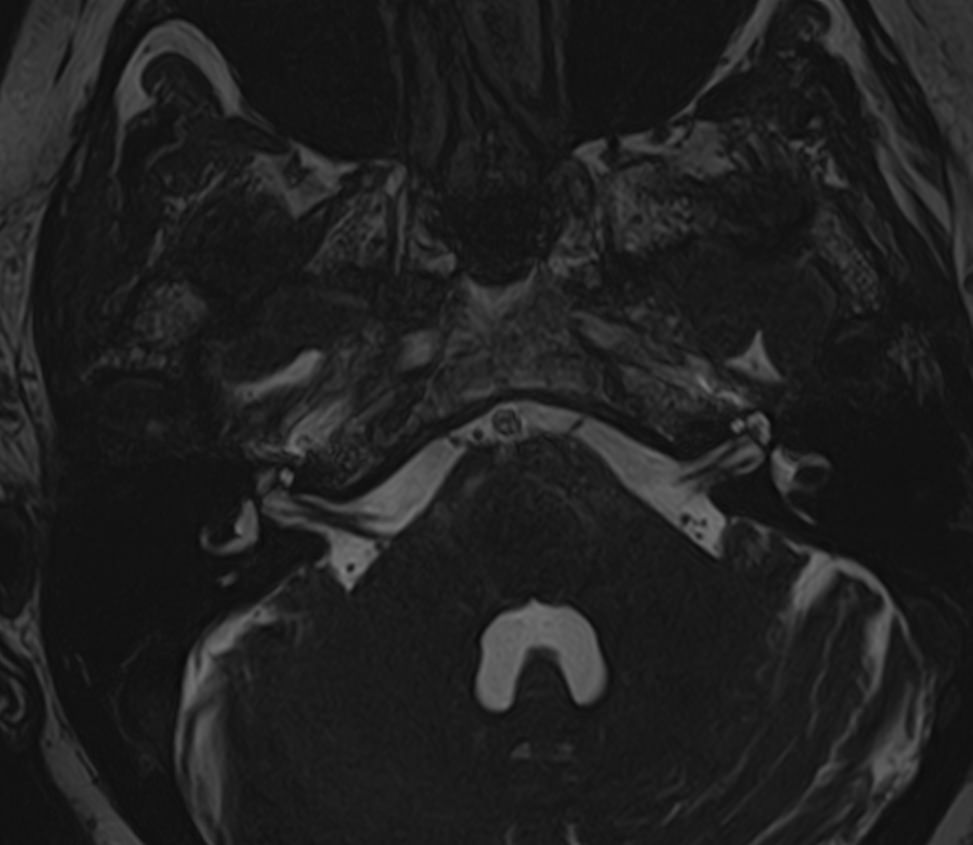

Магнитно-резонансная томография позволяет детально визуализировать изменения черепных нервов и прилегающих структур. В клинике «Доступная медицина» для точной диагностики причин поражения черепно-мозговых нервов применяется новейший высокопольный 32-канальный томограф TOSHIBA VANTAGE TITAN 1,5 Тесла, который обладает высокой чувствительностью и способностью определить минимальные изменения исследуемого органа.

Признаки нарушения функций ЧМН разнообразны. Причинами поражения могут быть серьезные заболевания, которые требуют незамедлительного обращения к врачу. Для установления точного диагноза в комплексе с другими методами используют МРТ и КТ головного мозга. Оба исследования имеют свои особенности. Компьютерная томография позволяет хорошо визуализировать изменения костной ткани. На МР-изображениях лучше просматриваются мягкотканные структуры, поэтому МРТ головного мозга с прицельным осмотром черепно-мозговых нервов является методом выбора в подобных случаях.